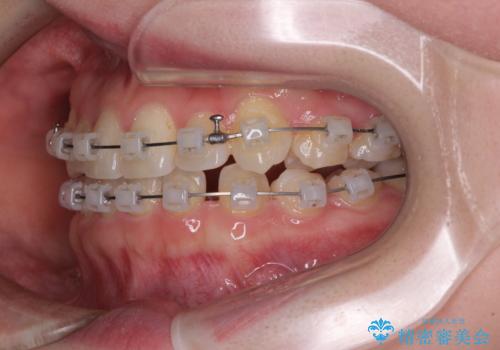

- クリアブラケット

- 1年3ヶ月

口腔内の状況を確認したところ、左右ともに下顎第二大臼歯が欠損しており、咬み合うべき上顎の第二大臼歯が著しく挺出していました。

挺出した大臼歯を元の位置に戻すことは現実的に難しいため抜歯することとし、補助装置とワイヤー装置により上顎歯列全体を後方に移動することとしました。

順調に後方移動することができ、わずか1年強で治療を終えることができました。